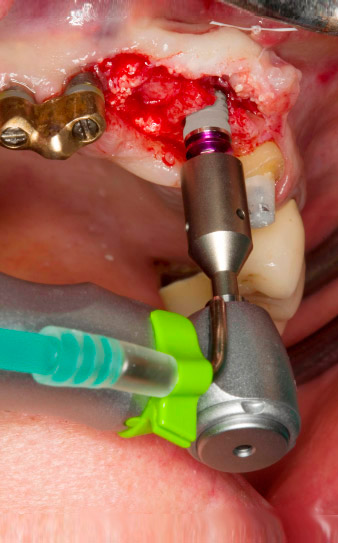

Motorized placement of the implant

Fig. 4: Motorized placement of the implant with the WS-75 L contra-angle handpiece at a ratio of 20:1 (programme P5).

Following primary healing, the soft tissues were shaped using the basally lined bridge. Two months later the site was exposed by a slightly palatal alveolar ridge incision (Fig 2). The dimensions of the alveolar bone proved to be sufficient at position 22. Figures 2 and 4 show the preparation of the implant bed, the tapping and the implantation using Implantmed.